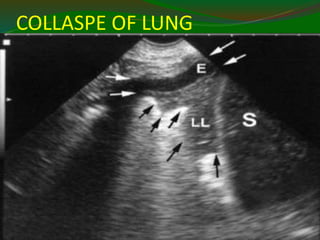

COLLASPE OF LUNG